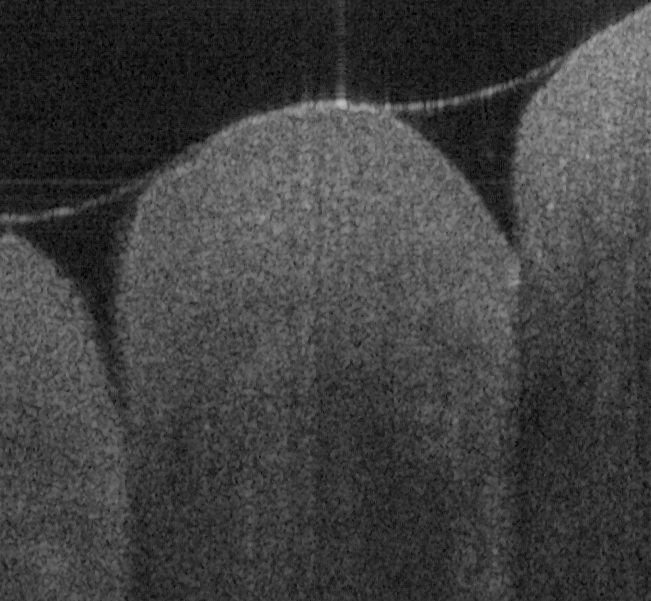

Fig. 16 (a) and (d) show SS-OCT images of human finger in vivo taken using fiber probes #

14 (working distance, depth of field and spot diameter of 1.2 mm 1.1 mm, and 27 m) and #

16 (working distance, depth of field and spot diameter of 0.9 mm 0.33 mm, and 16 m)

10

acquired by our catheter-based complex SS-OCT using our 3x3 Mach-Zehnder

interferometer with unbalanced differential detection technique with image size of 5x2mm.

The image depth shown in Fig. 16 (a) is slightly larger than that in Fig. 16 (b), but the image

is blurrier in Fig. 16 (a) than that in Fig. 16 (b), which taken by the probe with larger depth of

field and spot size. The image shown in Fig. 16 (b) has higher resolution than that in Fig. 16

(a), which can be seen clearly with finer structures in layer of epidermis (grey arrow), sweat

gland (white arrow), and blood vessel in subcutis layer (black arrow).

Fig. 16. In vivo human finger SS-OCT images taken with probe #14 (working distance, depth

of field and spot diameter of 1.2 mm 1.1 mm, and 27 m) and # 16 (working distance, depth

of field and spot diameter of 0.9 mm 0.33 mm, and 16 m) acquired by our catheter-based

complex SS-OCT using our 3x3 Mach-Zehnder interferometer with unbalanced differential

detection technique with image size of 5x2mm.